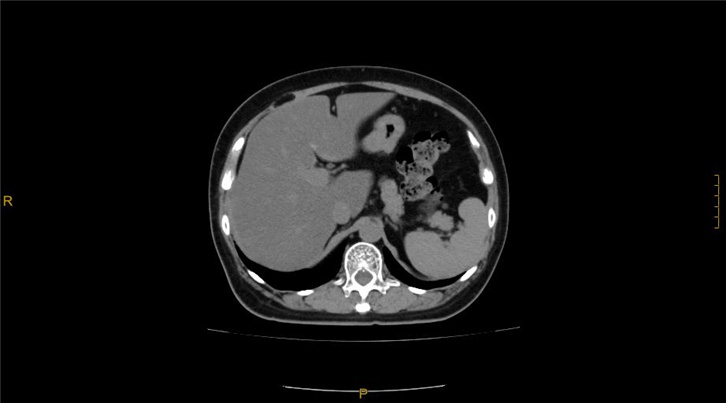

临床展示

腹部CTA三维重建